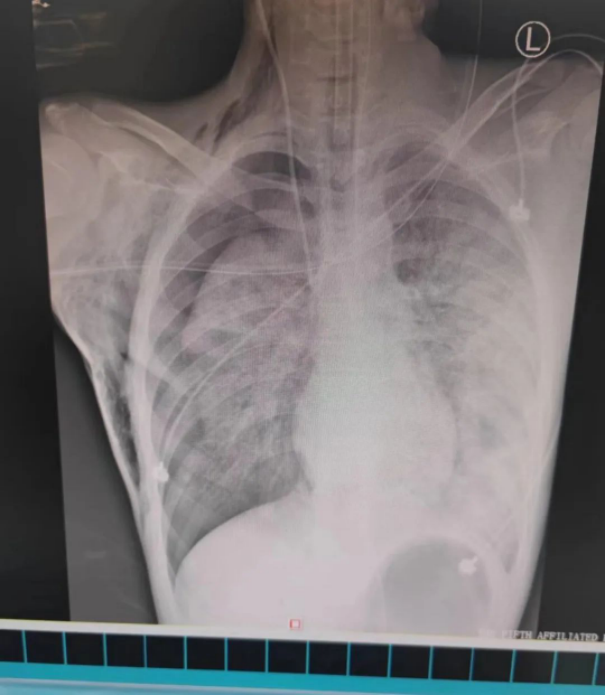

▲ 患者肺部情况恶化,右侧血气胸,肺部压缩超过50%,双侧肺挫伤,左肺几乎全为“白肺”。

经过几天的治疗,男孩的病情逐渐好转,肺部复张、双侧湿肺改善,颅脑伤情稳定,并顺利拔除了气管插管,但复查胸部CT提示双下肺仍有较多积血,如果不及时排出,将会导致机化和感染。